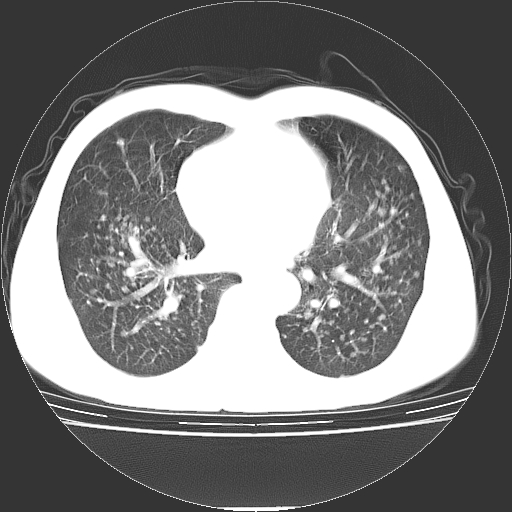

以下是引用yangyudong333在2008-4-29 5:38:00的发言:[br]比较典型的矽肺结节.支持[br]诊断依据:[br] 1.x线表现:[br] ①典型矽肺为多发直径 1~3mm 小结节,即矽结节,由胶原纤维和硅尘构成,可融合成团块,好发于上肺。[br] ②团块周围常有肺大泡。[br] ③胸内淋巴结增大、钙化。如肺门淋巴结呈蛋壳样钙化有助于与其他尘肺区别。[br] ④胸膜常广泛粘连、增厚。[br] 2.ct表现[br] ①两肺散在大小较为一致的小结节影,其密度较高,边界清楚。[br] ②小结节可融合为较大团块影,直径约 1cm ,甚至可达 10cm以上,易发生在上叶。[br] ③小结节周围常并有小叶中心气肿或弥漫性肺气肿。

以下是引用liuyue在2008-4-28 22:30:00的发言:[br]比较典型的矽肺结节.[br]请结合临床及化验除外矽肺合并肺结核之可能.